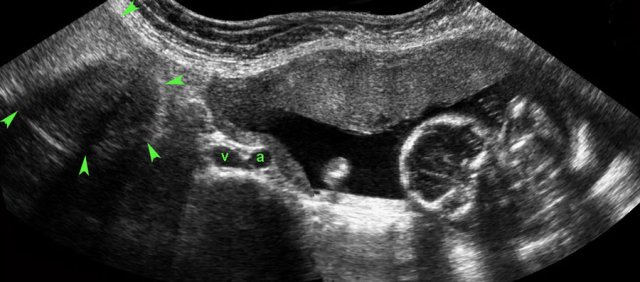

case 3

This patient was submitted for suspected perforated appendicitis.

US showed free fluid and to the right of the uterus (U.), a gestational sac containing a living fetus.

Fetal heartbeat was documented by TVUS with M-mode (right lower image).

A living fetus is found in less than 10 % of all ectopic pregnancies.